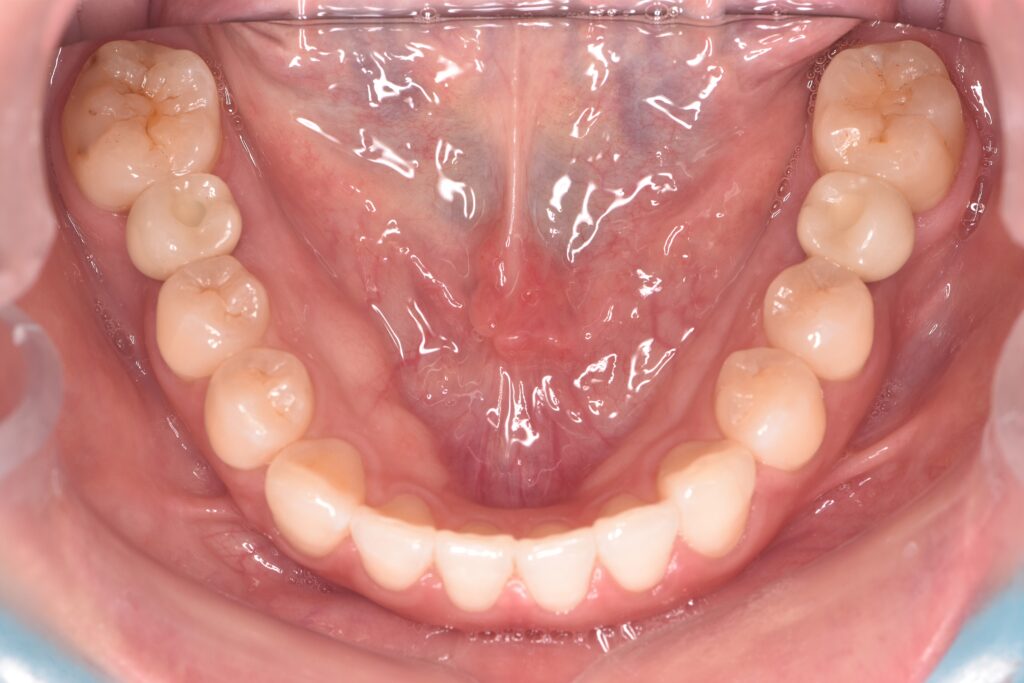

| 備考 | 右上の欠損部へのインプラントを希望で来院されました。 左下のブリッジの下にものが挟まりやすいとのことでブリッジ部分もインプラント埋入を希望されました。口腔内の銀歯も全て綺麗にやりかえたいとのことで、ダイレクトボンディングやセラミックインレーやジルコニアクラウンでやりかえていきました。 右上6番のインプラント埋入時にはソケットリフトで骨造成を行なっています。 見た目だけではなく噛みやすくなりとても満足されています。現在はエアフローのクリーニングやホワイトニングで通院されています。 |